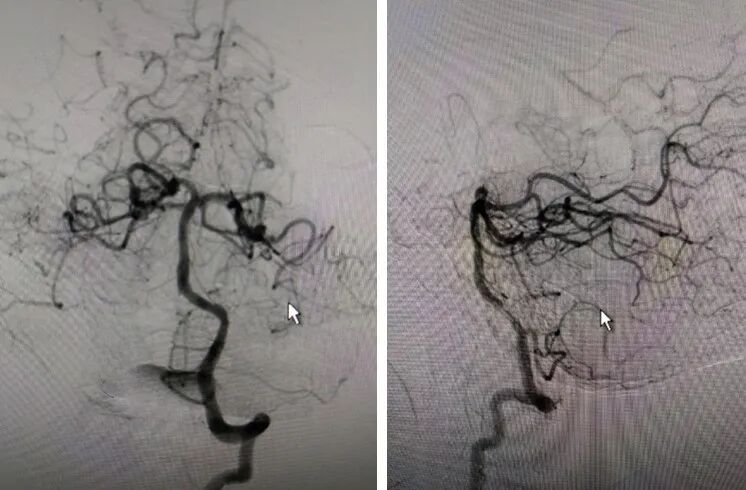

扩张后造影。

导丝怎么扩【载药时代 球扩天下】NOVA DES®颅内药物洗脱支架在大脑中动脉重度狭窄的应用二例!_https://www.jmylbn.com_新闻资讯_第27张

支架通过病变。

导丝怎么扩【载药时代 球扩天下】NOVA DES®颅内药物洗脱支架在大脑中动脉重度狭窄的应用二例!_https://www.jmylbn.com_新闻资讯_第28张

支架释放。

导丝怎么扩【载药时代 球扩天下】NOVA DES®颅内药物洗脱支架在大脑中动脉重度狭窄的应用二例!_https://www.jmylbn.com_新闻资讯_第29张

术后正位造影。

导丝怎么扩【载药时代 球扩天下】NOVA DES®颅内药物洗脱支架在大脑中动脉重度狭窄的应用二例!_https://www.jmylbn.com_新闻资讯_第30张

术后侧位造影

导丝怎么扩【载药时代 球扩天下】NOVA DES®颅内药物洗脱支架在大脑中动脉重度狭窄的应用二例!_https://www.jmylbn.com_新闻资讯_第31张